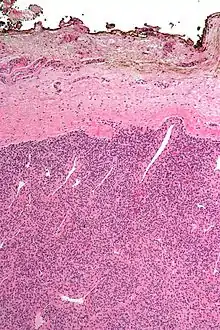

Surgical margin in a surgery report defines the visible margin or free edge of "normal" tissue seen by the surgeon with the naked eye. Surgical margin as read in a pathology report defines the histological measurement of normal or unaffected tissue surrounding the visible tumor under a microscope on a glass mounted histology section.[4][5] A "narrow" surgical margin implies that the tumor exists very close to the surgical margin, and a "wide" surgical margin implies the tumor exists far from the cut edge or the surgical margin. Narrow surgical margin using the bread loafing technique suggests that residual cancer might be left due to false negative error. A surgeon often will perform a second surgery if a narrow surgical margin is noted on a pathology report.